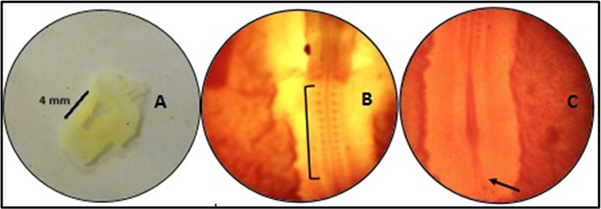

The day when eggs were placed in the incubator was taken as day 0. The eggs were manually rotated ½ turn twice daily and opened manually after 33 hours of incubation. The blastoderms were dissected out (Figure 1A), and whole mounts prepared. The dissected blastoderms were washed in normal saline in a watch glass, by gentle shaking. The washings removed most of the adherent yolk and gave relative clarity to blastoderm. It was then transferred to the glass slide and stretched out by the help of a blunt pointer. A drop of 70% ethanol was poured on it so that the plane of the tissue was, parallel with the plane of the slide. The mount was visualized directly under Olympus binocular light microscope to observe and compare the development and differentiation stages in both the groups (Figures 1B & 1C).

A: Blastoderm (4mm in length) dissected out.

B: Cranial end of whole mount approximating the HH Stage 10, showing 10 pairs of Somites (in parenthesis).

C: Caudal end of whole mount, showing regressing primitive streak. (Arrow)

Figure 1 Whole mount preparation of control Embryos.